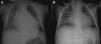

On admission he was apyretic, with pulse 190 bpm, respiratory rate 70–80 breaths per minute and oxygen saturation 95% in room air. His body weight was 6 kg (50th percentile). Physical examination revealed an infant of normal appearance but irritable and in respiratory distress. He was tachycardic, with an S3/S4 gallop rhythm. There were moist rales in the lung fields and chest wall retraction. The abdominal exam revealed hepatomegaly. The extremities displayed cyanosis and poor perfusion, with no edema. The chest X-ray showed cardiomegaly (cardiothoracic ratio 0.8) with pulmonary congestion (Figure 1A). The echocardiogram revealed a markedly enlarged left ventricular (LV) cavity with hypokinetic ventricular wall motion. LV end-diastolic diameter was 45 mm, LV end-systolic diameter was 40 mm, and fractional shortening (FS) was 5%, with no structural abnormalities (Figure 2). Electrocardiography showed sinus tachycardia (heart rate 190 bpm), LV hypertrophy and normal QTc.

Decreased serum calcium levels remained an issue while in the intensive care unit, requiring calcium boluses and drips to improve levels, which led us to study the patient's phosphorus–calcium metabolism. Hormone levels that were changed included elevated parathyroid hormone (231.8 pg/ml, reference value: 12–80 pg/ml), decreased 25-hydroxyvitamin D (5.94 ng/ml, reference value 11–70 ng/ml) and decreased 1,25 (OH)2 vitamin D3 (18.57 pg/ml, reference value: 20.2–46.2 pg/ml). There were no metabolic disorders on amino acid and organic acid tests. Calcium and vitamin D deficiency was confirmed and replacement with calcium and alfacalcidol (0.05 μg/kg/day) was started. As the levels of serum calcium increased to normal, the patient showed rapid recovery of cardiac function, normalization of LV dimensions and function on echocardiogram (Figure 3) and reduction of cardiomegaly on chest X-ray (Figure 1B). As the infant improved clinically, he was weaned to oral captopril, furosemide, spironolactone and digoxin. He was discharged on the 25th hospital day and followed in the outpatient clinic, with calcium gluconate and calcitriol replacement.